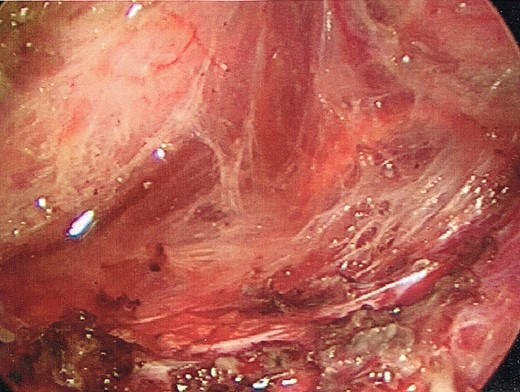

Once the dissection plane was entered, insufflation of the perirectal extraperitoneal space allowed for excellent exposure for a combination of blunt and Harmonic Scalpel dissection (Figs 4 and 5).

Enlargement of the proctotomy. The plane of dissection is visible (indicated by arrows), with the dome of the cyst seen at the bottom of the image.

The dome of the cyst is visible at the bottom of the image (indicated by arrow), with a dissection plane visualized above.